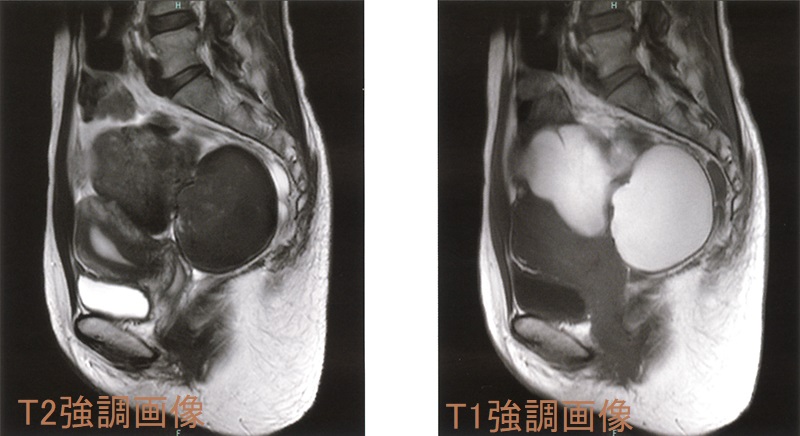

骨盤部単純MRI 画像では、背側が低信号になる(shading)。

チョコレートのう胞(卵巣子宮内膜症)は、0.7-1.6%が子宮内膜症関連卵巣癌(EAOC)に悪性転換します(Reproduction. 2004 Mar; 127(3):293-304.)。組織型は明細胞癌、類内膜癌など。チョコレートのう胞(卵巣子宮内膜症)の既往がある女性において、衣服がきつくなるなど腹部膨満感・下腹部膨隆の自覚症状がおこり、下腹部に可動性のない腫瘤を触れた場合、子宮内膜症関連卵巣癌(EAOC)が疑われます。

子宮内膜症関連卵巣癌(EAOC)の危険因子は、過剰なエストロゲン刺激に関連する

- 甲状腺疾患